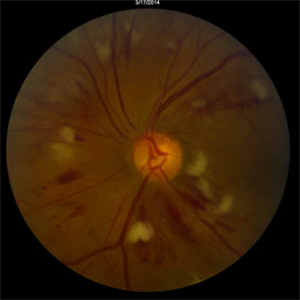

Candida Albicans Endophthalmitis

Mar 17 2013 by David Callanan, MD

28-year-old male with 1 week history of decreased vision. Following biopsy and treatment, patient admitted to illicit intravenous drug use.

Condition/keywords: endogenous endophthalmitis